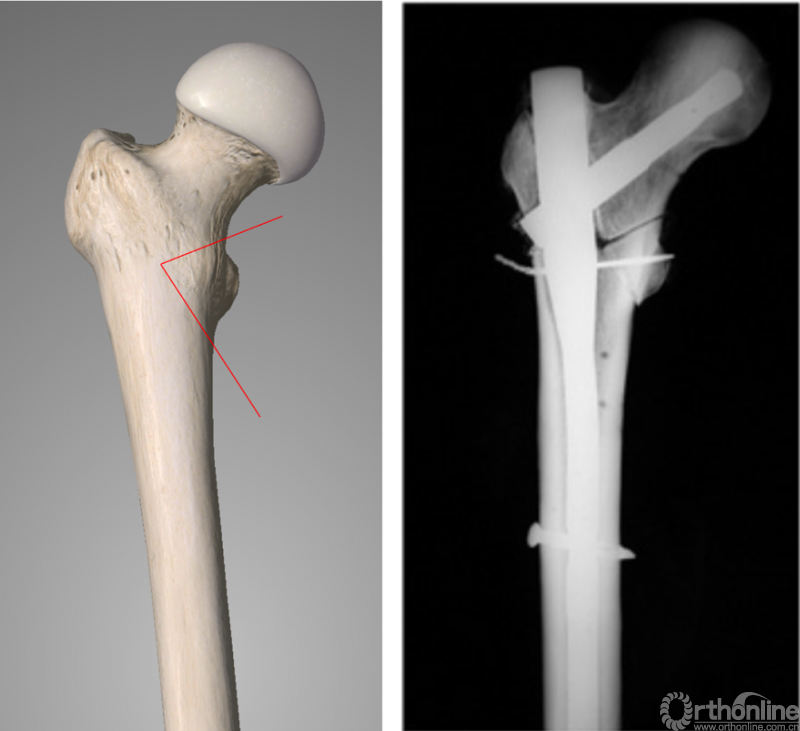

既往的生物力学研究显示,内侧壁的缺损(或者说内侧壁骨折的存在)会造成粗隆间骨折模型应力强度的明显下降。但近期相关的临床病例回顾性研究显示,当使用髓外固定系统(DHS)或髓内钉(PFNA)治疗股骨粗隆间骨折时,内侧壁骨折并不显著增加内固定的失败率。我们认为,在普遍使用的生物力学模型中,内侧壁骨折块是由摆锯截除的楔形骨块,这与临床多见的内侧壁骨折块并不相同(图4),这可能是生物力学实验结果与临床回顾性研究结果并不相符的原因。

图4:生物力学模型的内侧壁截骨范围